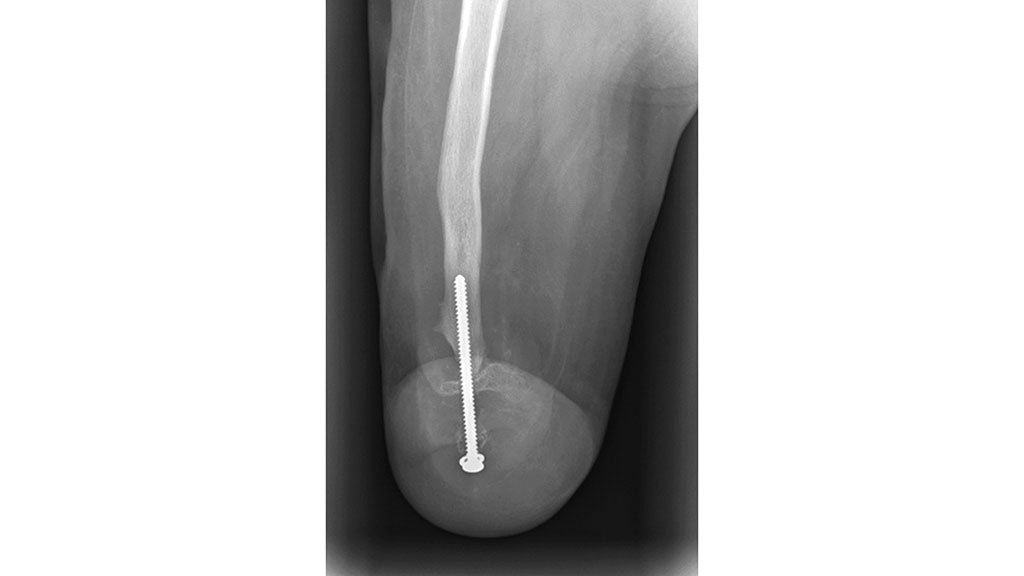

Hierbei handelt es sich um einen 15-jährigen Jungen. Zu Beginn versuchte man, die angeborene Femurdysplasie mit mehreren orthoprothetischen Versorgungen auszugleichen (Abb. 16). Man entschied sich nach mehreren problematischen Versorgungen zu einer Umkehrplastik (Typ B3a nach Prof. Winkelmann).

Da die Entwicklung des Patienten noch unklar war, entschieden sich die versorgenden Techniker, seinen eigenen Fuß in der Normalstellung zu belassen. Zu dem damaligen Zeitpunkt war der Plan für das Procedere, das Femur zu verlängern, um die Längendifferenz auszugleichen. Hierfür wurde eine Orthoprothese gebaut. Um die Hüftsituation zu stabilisieren (Abb. 17), entschied man sich für einen rigiden Beckenkorb und eine bewegliche Stahlschiene als Hüftgelenk. Zur Optimierung des Sitzens beschloss das Team, ein Kniegelenk mit Federvorbringer zu verwenden (Abb. 18). Als Fußpassteil wurde ein Kinder-Dynamikfuß eingesetzt.